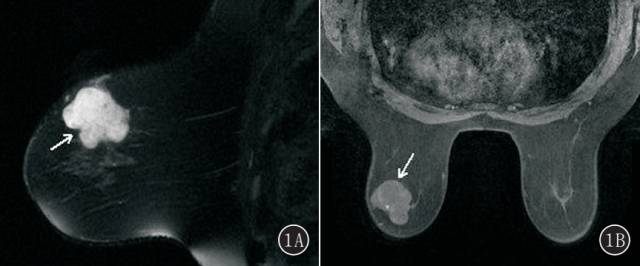

图2A~E 女,54 岁,右侧乳腺单纯型黏液腺癌。 A. T2 WI 右侧乳腺外下象限卵圆形肿块(白箭头),明显高信号,边缘多发细毛刺(黑箭头);B. T1 WI 平扫呈周边环形等信号,中心不均匀低信号(白箭头),边缘多发细毛刺(黑箭头);C. 动态增强呈环形强化(白箭头),强化环厚度不均匀,边缘多发细毛刺(黑箭头);D. 时间-信号强度曲线呈持续型;E. DWI 呈明显高信号(白箭头)